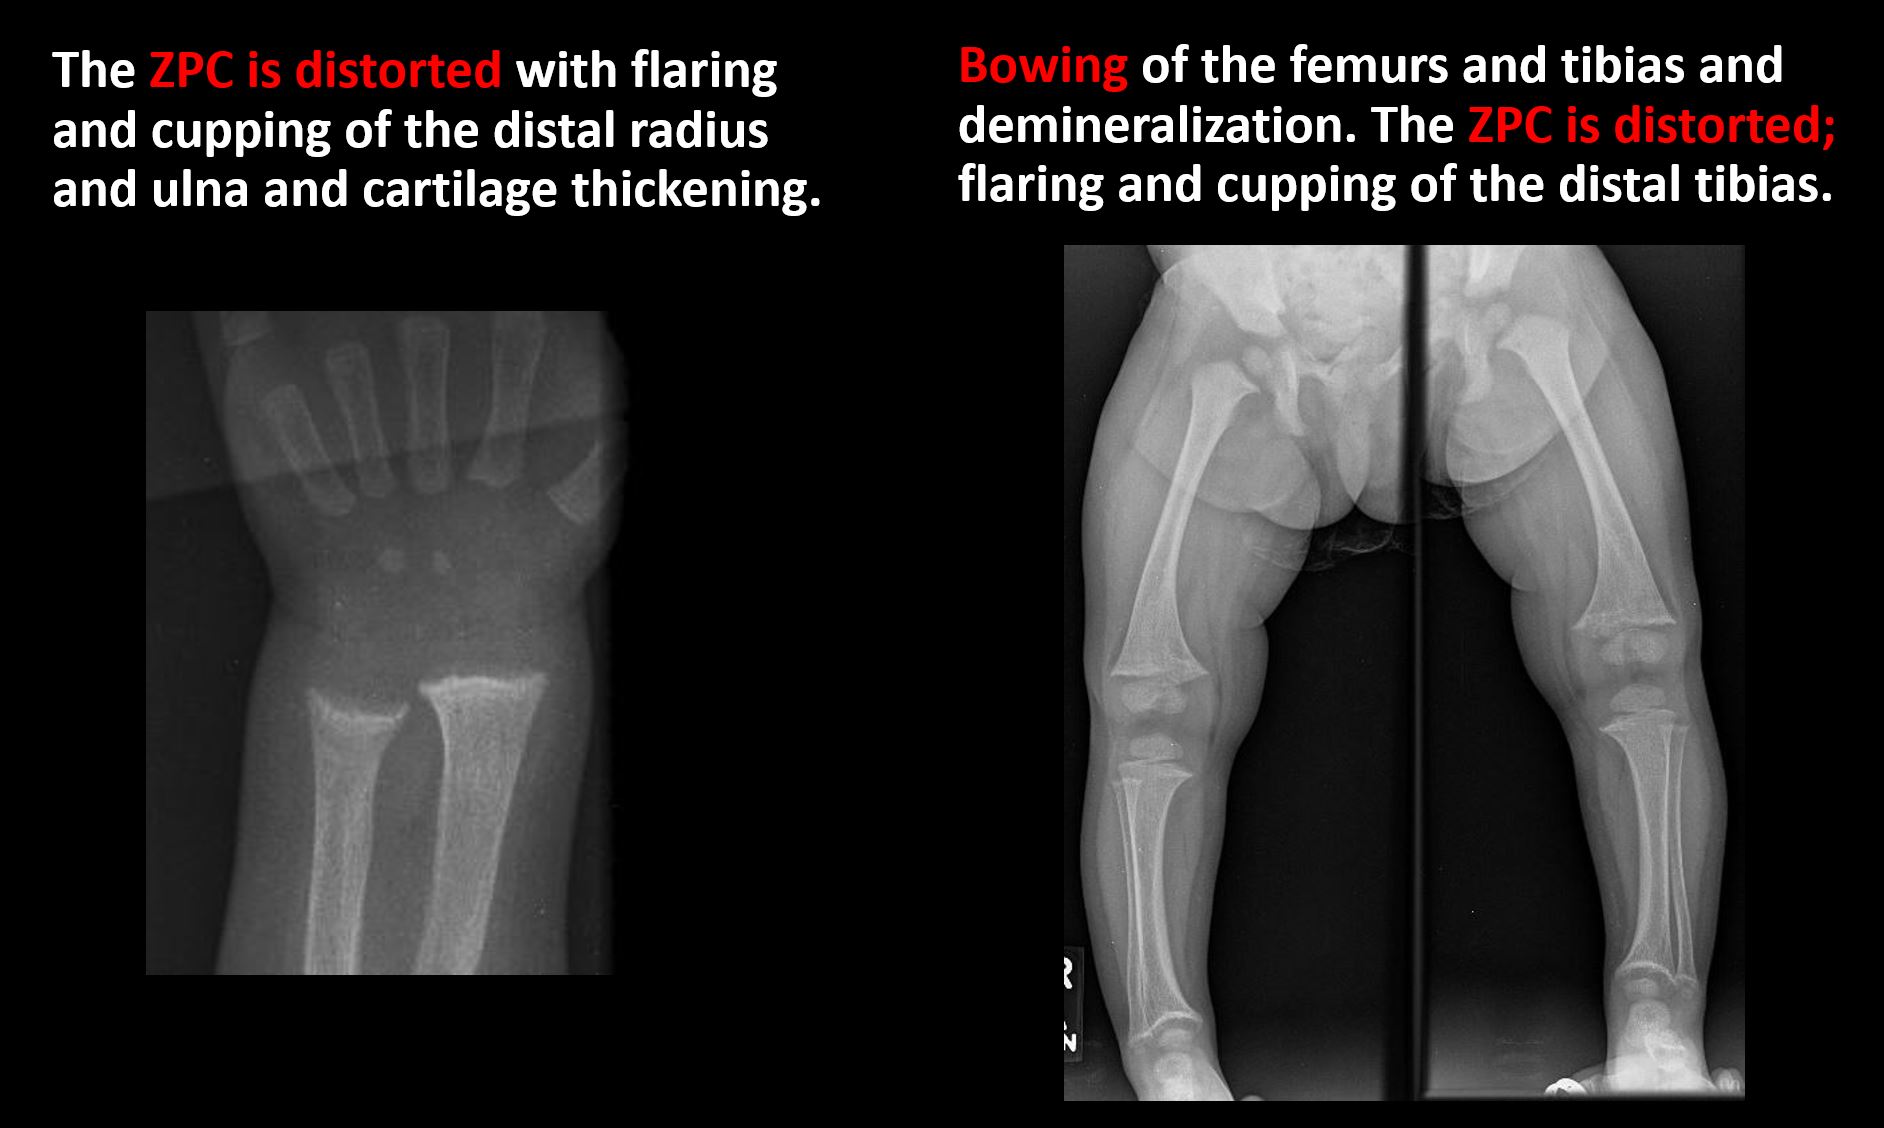

There is metaphyseal abnormality (lucencies, increased density, erosion) which may be from something other than injury such as stress, metabolic disease (e.g. rickets), neoplasm (e.g. leukemia), heavy metals, inflammation, or infection. [Yes/No]

Overall bone density is increased or decreased with or without thinning or thickening of the cortical or cancellous bone. [Yes/No]